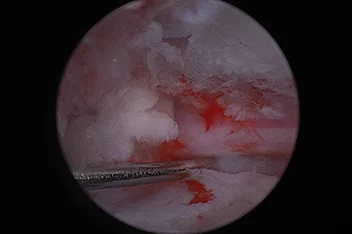

관절경

개,고양이 들은 다양한 관절질환이 존재하고, 복합적으로 존재하는 경우도 빈번합니다.

정확한 진단이 나지 않은 뒤 수술을 하게되면 증상개선이 더디거나 개선이 안될 수 있어, 정확한 진단이 필요합니다.

관절의 경우 X-ray 촬영등으로 진단의 한계가 명확하며, 상위 검사인 CT, MRI 촬영으로도 진단의 한계가 있습니다.

이때 관절경은 내부 구조물들을 직접 시각화 하여 보다 정확한 관절의 상태를 확인하고 진단할 수 있으며, 진단과 치료를 동시에 진행하는 경우도 있습니다. 대표적으로 십자인대단열(CCLR), 골연골염(OCD), 자뼈꿈치돌치유합부전(UAP), 내측관상돌기질환(MCD) 등에 활용될 수있습니다.

관절경 팔꿈치관절(Elbow) 확인

관절경 무릎관절(Stifle) 확인 (반월판 및 십자인대)

* 리본동물의료센터 케이스 사진으로 무단 복제 및 도용을 금지합니다.